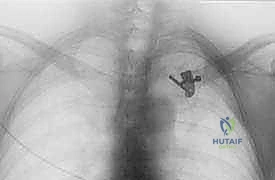

- الأشعة السينية (X-rays): يتم إجراء صور شعاعية خاصة (مثل وضعية Serendipity view). ومع ذلك، فإن الأشعة العادية غالباً ما تكون غير كافية بسبب تداخل ظلال الأضلاع والعمود الفقري مع المفصل.

- التصوير المقطعي المحوسب (CT Scan) - المعيار الذهبي: يؤكد الدكتور هطيف أن الأشعة المقطعية، خاصة مع إعادة البناء ثلاثي الأبعاد (3D Reconstruction)، هي الإجراء الحاسم. فهي تحدد بدقة متناهية اتجاه الخلع، وجود كسور مصاحبة، ومدى قرب الترقوة من الهياكل الحيوية.